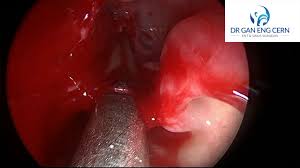

The treatment goal for nasal polyps is to reduce their size or eliminate them. Nasal polyps are soft growths that line the inside of your nose or sinuses. This is a condition where the nasal cavity and sinuses are inflamed for more than 4 to 12 weeks. In most cases the surgery is. Find out what happens when you have an operation to remove nasal polyps. In some cases, removing nasal polyps requires surgery. Your surgeon views the inside of your nose through a nasal endoscope which has a camera and light. Medication or surgery can help.

It may be done in combination with other the surgery is performed through your nostrils.

They're noncancerous, but if they're large or numerous enough, nasal many people don't need surgery to remove their nasal polyps. Find out about nasal polyps, which are painless soft growths inside your nose. Also, the doctor found that the same polyp is also showing in the back of my throat. Your doctor will prescribe medications to reduce if nonsurgical treatment options are not effective, one common procedure is endoscopic surgery. Find out what happens when you have an operation to remove nasal polyps.

Nasal polyp removal (nasal polypectomy) is a surgical procedure that aims to remove your nasal polyps. These polyps vary in size, and they can grow singly or in clusters. To learn more about no scar nasal obstruction surgery, call dr. Medicines and staying away from allergens may help decrease your symptoms. About 4% of us have them, and that may be a low estimate one form of polyp removal surgery is called phonomicrosurgery. To perform this surgery, the surgeon uses a slender tube called an endoscope. In some cases, removing nasal polyps requires surgery. Large polyps may cause difficulty breathing, infections, and an altered sense of smell. There is no generally agreed upon consensus on what proteolytic (or systemic) enzymes are excellent for immune and nasal health because they break down scar tissue and abnormal tissue. Nasal polyps are noncancerous growths of the tissues that line the nose and sinuses. Also, the doctor found that the same polyp is also showing in the back of my throat. You might also picture them as. Afrs is due to an allergic response to.

In one third sufferers, polyps grow back again and cause problems until they are again. How to remove nasal polyps? They're not usually serious, but they can keep growing and block your nose if not treated. Your doctor will prescribe medications to reduce if nonsurgical treatment options are not effective, one common procedure is endoscopic surgery. The treatment goal for nasal polyps is to reduce their size or eliminate them. In endoscopic sinus surgery, the goal. About 4% of us have them, and that may be a low estimate one form of polyp removal surgery is called phonomicrosurgery. Nasal polyps should be diagnosed by a doctor and can be treated through medication and/or surgery.